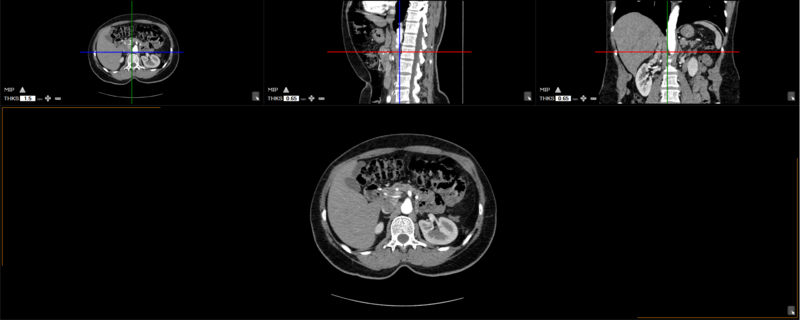

The user can choose from any of these predefined viewing protocols within the MPR mode:

Here are the different viewing protocols you can choose from: